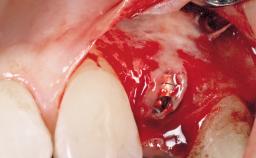

A 39-year-old male patient presented with a chief complaint of discomfort and gingival discoloration around his maxillary left central incisor. He was in good general health and was a non-smoker. His past dental history was significant because of the traumatic fracture of tooth 21 in a sporting accident at age 13. Initial dental treatment included endodontic therapy and a full-coverage restoration. The patient became symptomatic 5 years later, when structural failure of the tooth resulted in the dislodgment of the crown. Endodontic retreatment, apical surgery, and post-and-core restoration were performed.

Bone Augmentation Horizontal|Staged

Augmentation Materials Xenogenous|Membrane

Bone Volume Deficient horizontally, requiring prior grafting